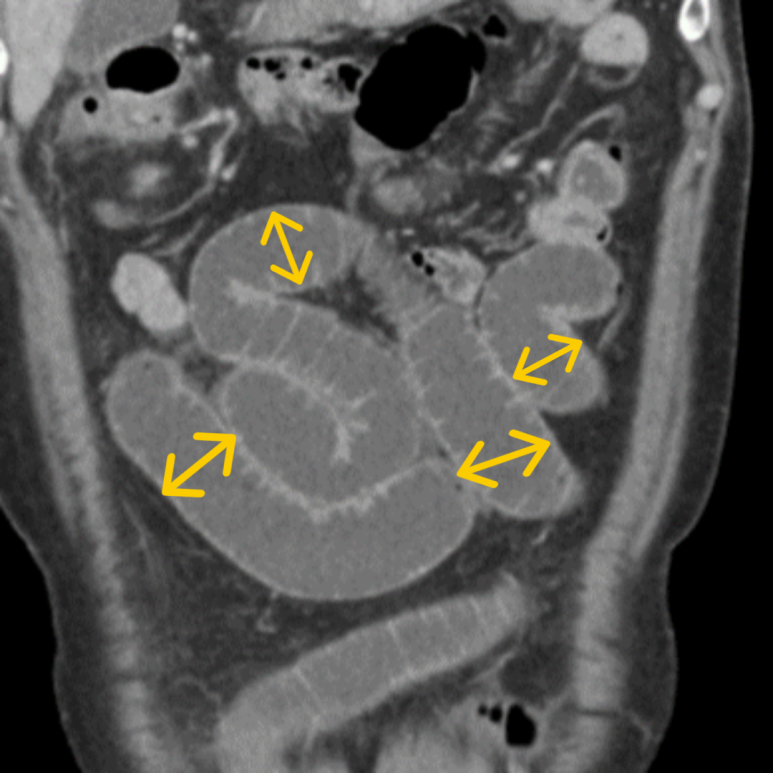

게실염, 충수염, 하복부통증 증상의 원인을 정확하고 신속하게 진단합니다.

게실염, 충수염, 하복부통증에 통해 관련 사례를 확인하실 수 있습니다.